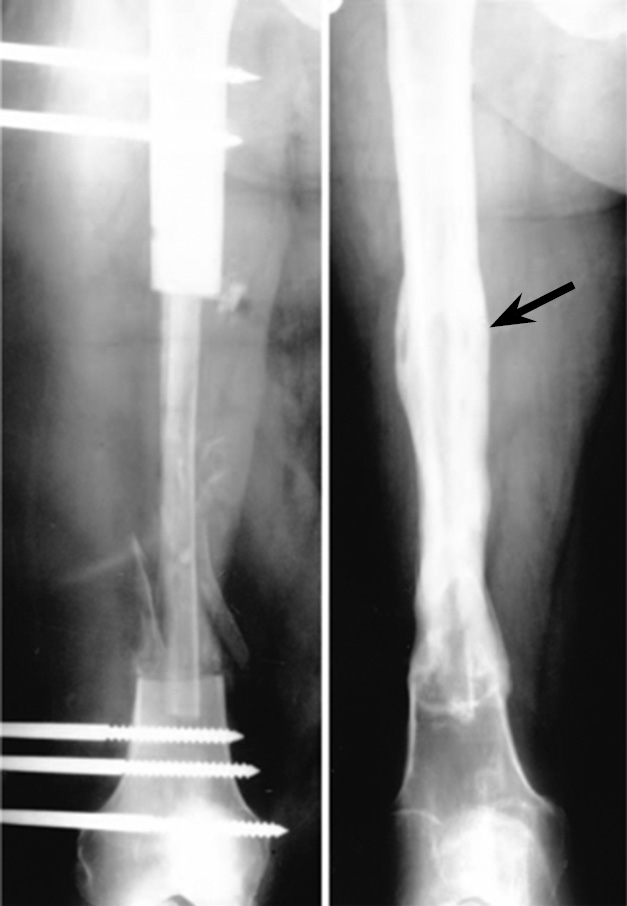

Vascularized grafts undergo the same adaptation and remodeling as the native bone [26]. Given this property of bone tissue, with appropriate load on the graft, the grafted bone can grow in thickness to the size of a normal bone (Fig. 1) [26, 29].

Fig. 1. Radiographs of a vascularized fibula autograft at the site of the femur defect immediately after surgery and after 9 months (the red arrow indicates the line along which the graft was incorporated) [29]